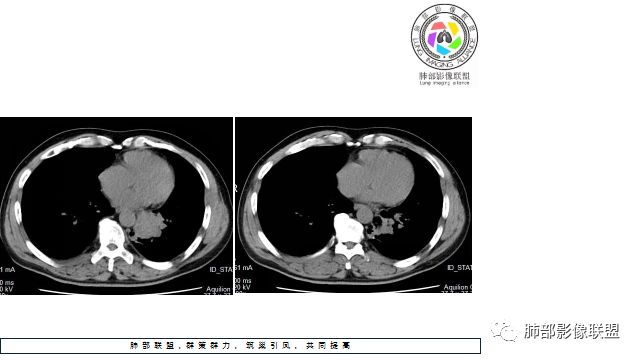

1.左下肺门区巨大肿块,支气管显示不清,轻度阻塞性炎症,没有明显肺不张,提示管腔受压狭窄可能性大于堵塞,这较少见于鳞癌。

2.病灶边缘光滑,未见明显分叶、毛刺,未见明显强化,这符合腺癌影像学特点,却符合神经内分泌癌表现。

3.病灶内密度均匀,轻到中度均匀强化,大病灶未见明显液化坏死区及空洞,不符合鳞癌而符合小细胞肺癌特点。

4.病灶内有肺动脉走形,血管局部受压,未见破坏,病灶乏血供,呈血管包埋或血管造影征;侵袭性力强及破坏力弱、血管漂浮都符合SCLC,所以鳞癌的可能性也不大。

5.左肺门块影或淋巴结肿大,竭力挤兑肺门血管结构,呈冰冻肺门;有时候SCLC可以单独呈现冰冻肺门,而没有没有冰冻纵隔。